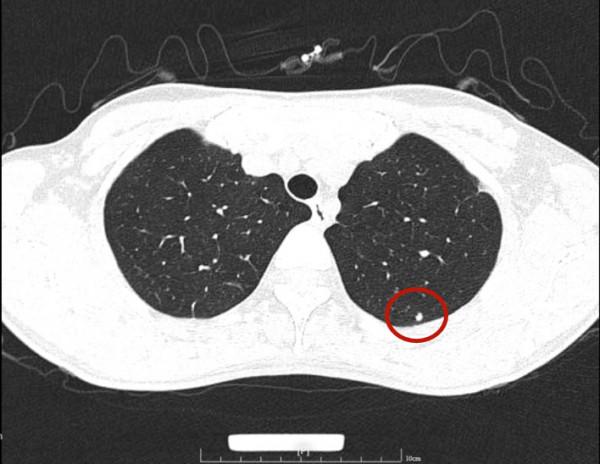

那麼多結節,基本上都是實性,分佈兩肺,形態不似圓形或類圓形的轉移瘤。是什麼呢?我們是不是一定要弄明白到底是什麼病?其實我覺得有時並不一定要弄清楚,所以我回復的意見如下:我認為我們看病,有時候可以從結果來反推,從而考慮是不是干預治療。比如這個病例的兩肺多髮結節,我看沒有一個是主病灶,也就是說“明顯考慮惡性的,其他考慮是這個病灶轉移的”這種樣子。那麼這些實性小結節,可能是:1、良性結節:包括慢性炎,纖維增生、肺內淋巴結、風溼結節、肉芽腫、隱球菌等各種可能性。但只要是良性,不處理不影響生命,也沒什麼不舒服,只需關注著,定期複查就可以了;2、腫瘤多發轉移:不管原發灶在哪裡,如果兩肺這麼多轉移,你再怎麼治療,預後也不好,現在還不是典型的腫瘤,也未見明顯的原發部位,遲點有進展再考慮又有多少區別呢?3、結核:即使真是結核,沒有明顯症狀的情況下,很多人自己得過結核也不自知,意思是說,如果痰找結核菌陰性,不是活動性肺結核,沒有症狀,不治療也沒什麼關係,也是隻需要定期複查。所以你的病例,我的意見是:1、形態數目不像惡性;2、不需深究到底是什麼;3、把診斷交給時間來決定,建議每4-6個月複查平掃,有變化時展再考慮活檢或干預,否則先不去管它。